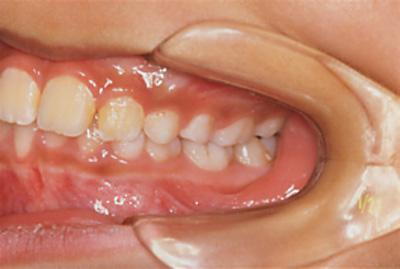

男児/下顎が大きく右にずれて咬んでいる

| 主訴 | 前歯がずれている |

|---|---|

| 診断名 | 上顎狭窄歯列による下顎変位症例(右側歯列交差咬合) |

| 初診時年齢 | 7歳6か月 |

| 装置名 | 上顎拡大装置、バイオネーター |

| 抜歯非抜歯 | 非抜歯 |

| 治療期間 | 3年9か月 |

| 費用の目安 | 治療費330,000円、保定費0円、処置料3,300円×45回(税込み) |

| リスク副作用 | 前歯のかみ合わせが治った後、犬歯小臼歯の生えかわりに数年かかります。 顔面の非対称が残る場合があります。 |